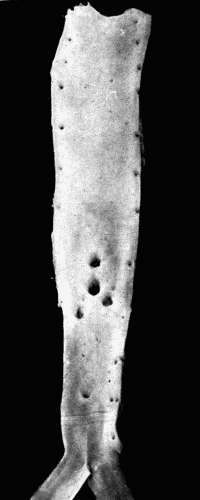

Fig. 5.—Normal aorta. Compare with Fig. 3. Note the perfectly smooth, glossy appearance of the intima. The openings of all the intercostal arteries are distinctly seen. In the recent state this artery was highly elastic, capable of much stretching both transversely and longitudinally. Fig. 5.—Normal aorta. Compare with Fig. 3. Note the perfectly smooth, glossy appearance of the intima. The openings of all the intercostal arteries are distinctly seen. In the recent state this artery was highly elastic, capable of much stretching both transversely and longitudinally.

Thus the sclerosis of the radials of such an extent that these arteries are easily palpable, appears to be a different process from that of the sclerosis in the aorta, yet fundamentally it is the same. The difference lies in the anatomic structure of the two vessels, and possibly also in the degree of stretching and strain to which the vessels are subjected at every heart beat. In the radial artery the media as usual is affected first. The muscle cells undergo degeneration and either marked thickening takes place or sacculation results, depending upon the severity of the exciting cause. Calcification of the media is common. This occasionally takes the form of rings encircling the vessel, and gives to the examining finger the sensation of feeling a string of fine beads. There may be calcification of the subintimal tissue without deposits of lime salts in the media, but this is more commonly found in the larger arteries. When the calcification occurs in plates through the media, the well known pipe stem vessel is produced. (Fig. 6.)

Fig. 6.—Radiogram of a man aged seventy-five, showing calcification of both radial and ulnar arteries. Fig. 6.—Radiogram of a man aged seventy-five, showing calcification of both radial and ulnar arteries.